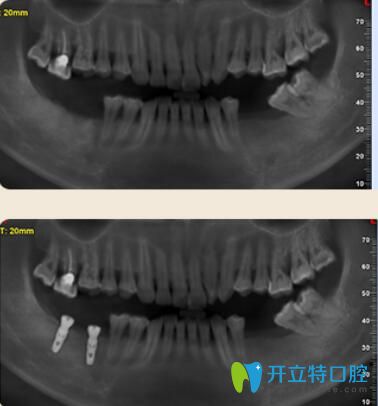

案例二:多顆牙齒缺失的胡先生種植牙案例

胡先生年齡不是特別大,但是已經(jīng)缺牙多顆,不僅影響日常飲食,對發(fā)音也有一定的影響。聽朋友說好佰年口腔的數(shù)字化種植技術(shù)很先進的,于是來到了好佰年。

多顆牙齒缺失的胡先生種植牙案例

因為胡先生對疼痛非常敏感。所以在種植時候結(jié)合睡眠技術(shù),種牙過程中沒有任何的不適和疼痛感,半小時后種好牙齒,隨便吃,再也不用擔(dān)心吃硬東西了!

東莞好佰年口腔多顆牙種植案例